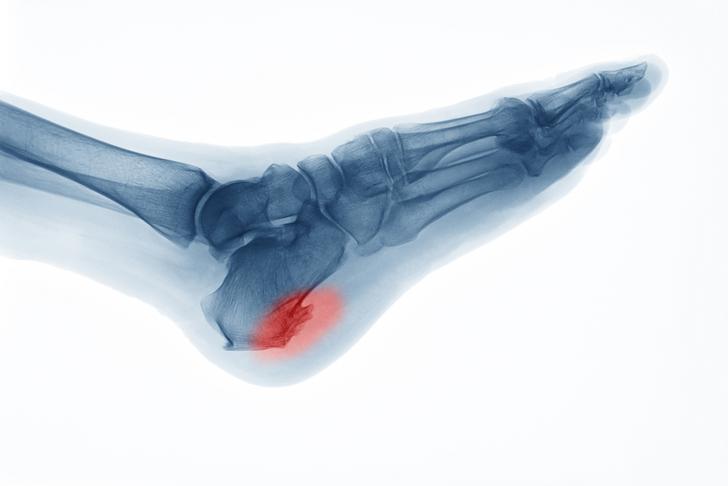

Bone Spurs

Bone spurs, or osteophytes, are bony growths that can develop around the edges of the affected joints. These growths can cause pain and may further limit joint movement[[2]].